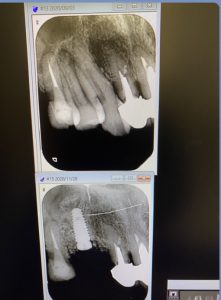

2症例共にソケットリフト法を併用するオペです。

(午前オペ/抜歯即時埋入)

患者さんにとって、抜歯と同時にインプラント埋入はオペが一度で済む利点がありますね